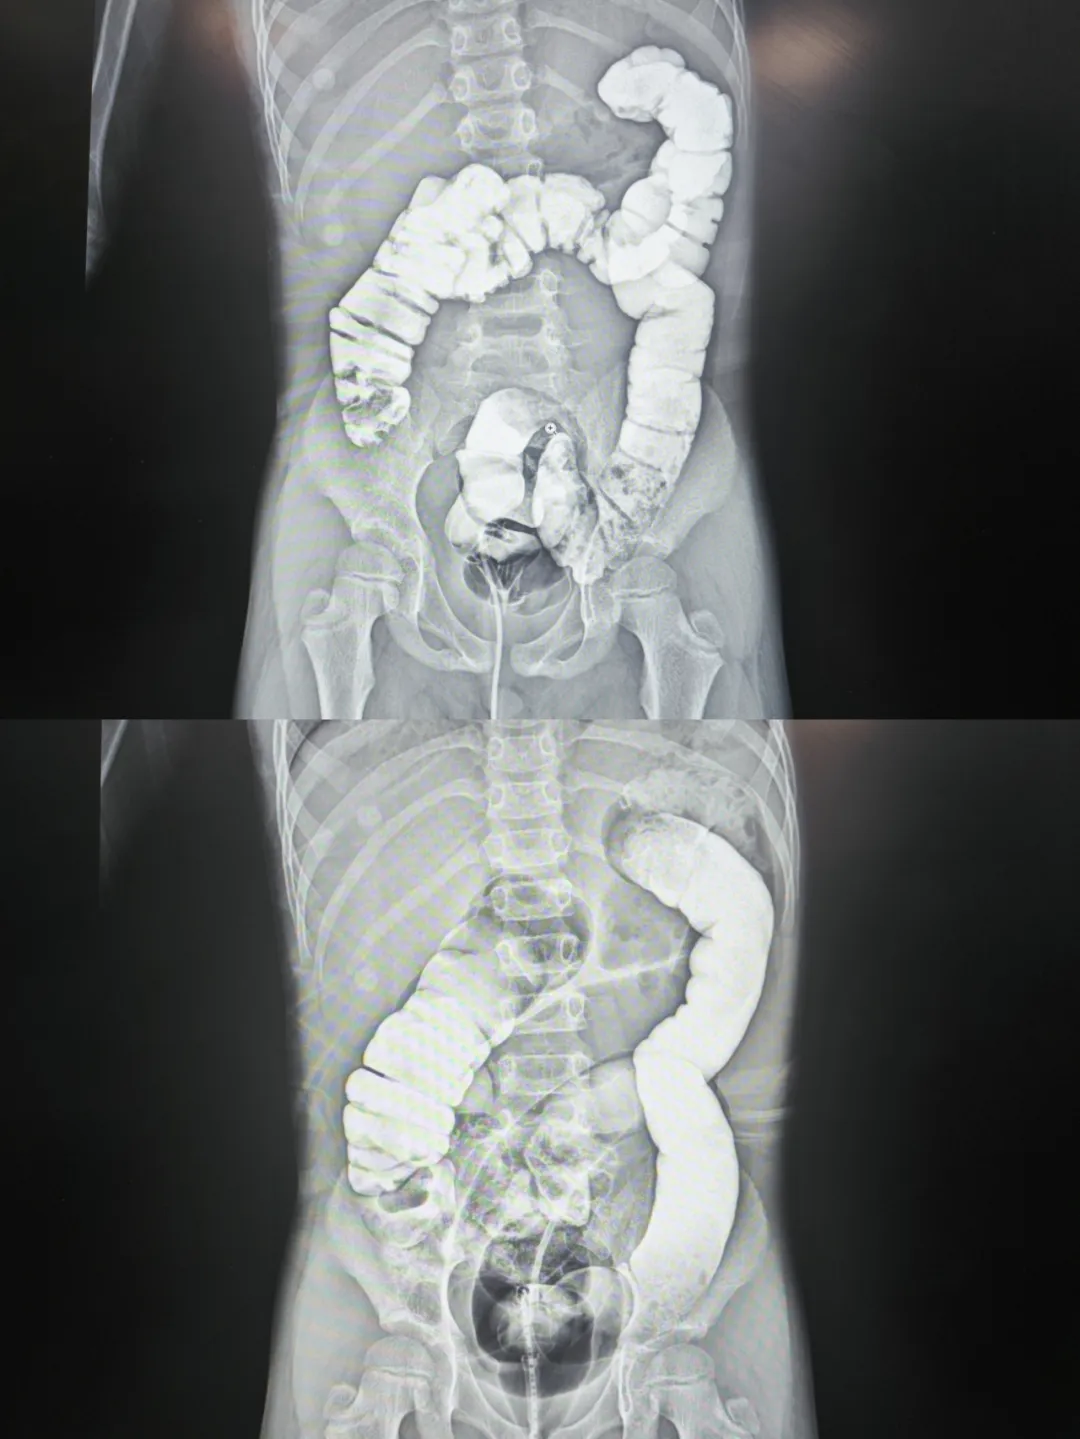

病例1

回盲部复位、小肠逆行充气,复位成功